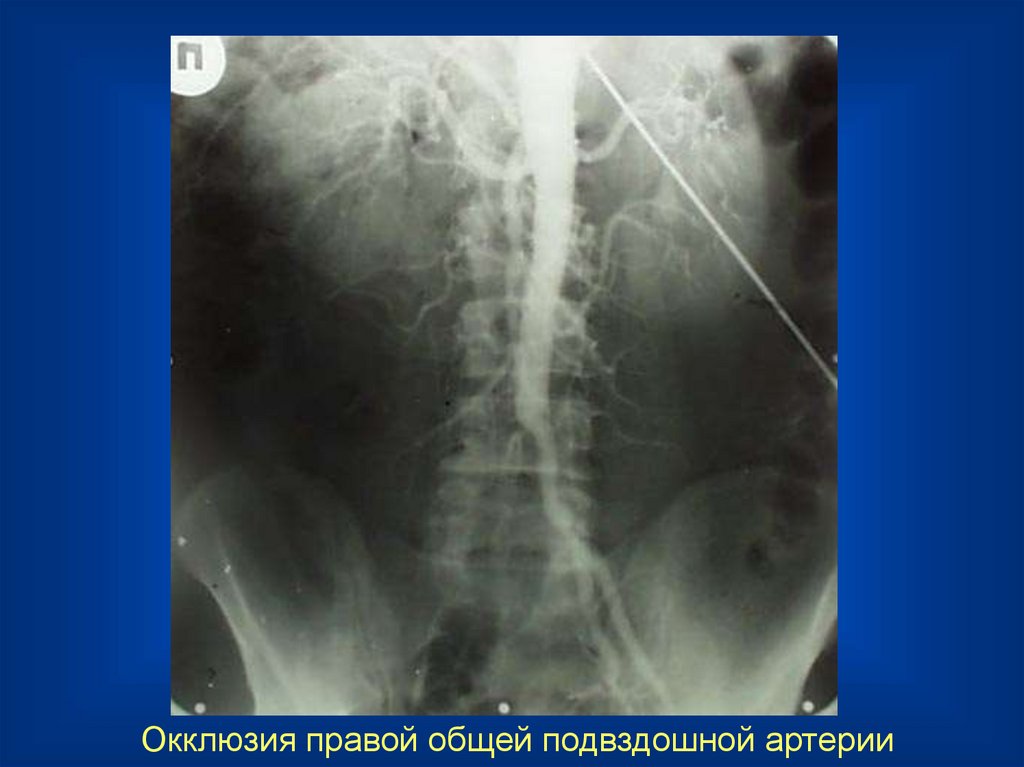

Окклюзия правой общей подвздошной артерии